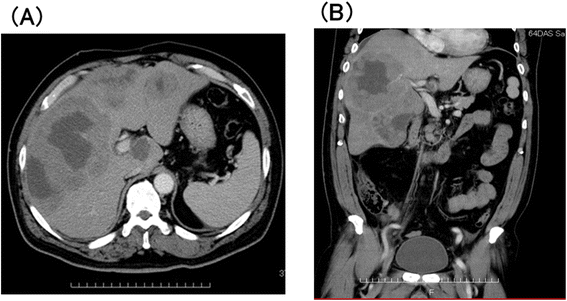

本环节的实验目的是明确肝脏病变的位置、大小及全身累及情况,排除其他部位淋巴瘤累及。方法细节为采用腹部增强计算机断层扫描(Contrast-Enhanced Computed Tomography, CECT)、超声检查,同时行脑、颈、胸、盆腔CECT及骨髓穿刺活检。结果解读显示,腹部CECT显示右肝多发不规则结节状肿块,最大直径达13cm(图1),全身其他部位无肿大淋巴结或肿块,骨髓穿刺未发现淋巴瘤细胞浸润;确诊病变为原发性肝脏病变,排除全身淋巴瘤累及肝脏的可能,为PHL的诊断提供了影像学依据。产品关联:文献未提及具体实验产品,领域常规使用64排及以上CT扫描仪、彩色多普勒超声诊断仪进行影像学检查。